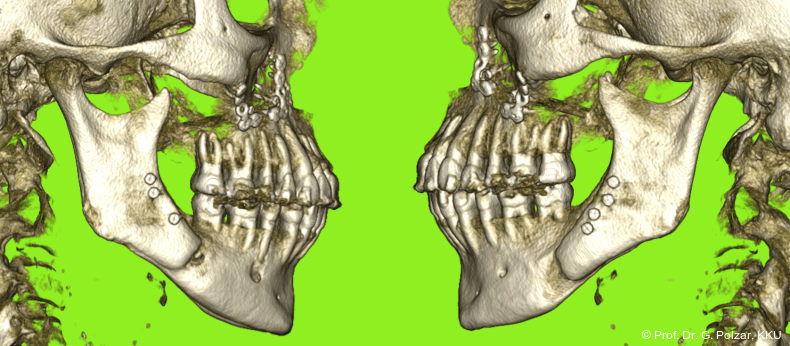

KG-Position: Die 3D-Ansicht im DVT zeigt eine vorverlagerte UK-Position bei neutraler Okklusion (Abb. 4a+b).

Im Sagittalschnitt zeigen beide Kiefergelenke eine deutlich anteriore Position. Der dorsokraniale Abstand betrug rechts 7,0 mm und links 5,8 mm. In der PEP waren sie im lateralen Bereich ca. 1 mm kleiner als in der Mitte der Sagittalprojektion (Abb. 6a–d).

Diese deutlich anteriore Gelenkposition im Neutralbiss ließ den Verdacht auf einen Sunday Bite zu. Das heißt, die Patientin schob den Unterkiefer aktiv nach vorne, um damit schönere Schneidezahnkontakte bzw. eine vermeintlich neutrale Okklusion zu erreichen. Nach mühsamen Lockerungsübungen gelang es der Patientin, auch in die zen­trale Kiefergelenkposition zu wechseln. So zeigte sich das ganze Ausmaß der Malokklusion. In neutraler KG-Position hatte die Patientin eine sagittale Frontzahnstufe von ca. 7 mm mit 1 PB Klasse II-Okklusion im Seitenzahn­bereich (Abb.5a+b, 7a–c).